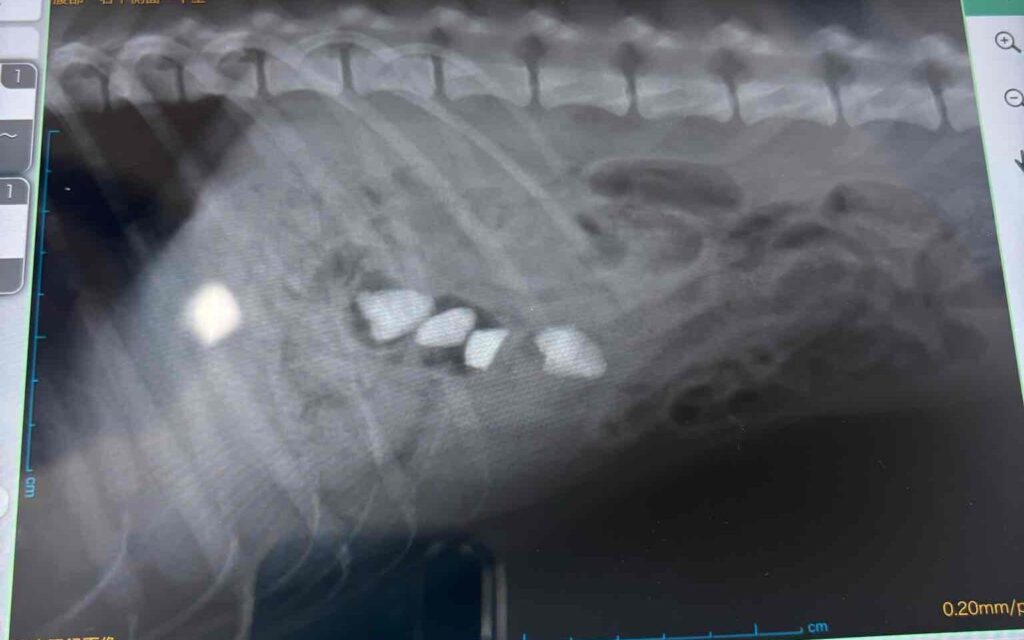

ちょうどレントゲン写真が残っていたので、参考までに掲載しますね。

※以下に、動物病院で撮影したレントゲン画像を掲載しています。

痛々しい表現はありませんが、医療画像が苦手な方は閲覧をお控えください。

動物病院では

「お腹の中で詰まったら命に関わる」

と、かなり強めに言われています。